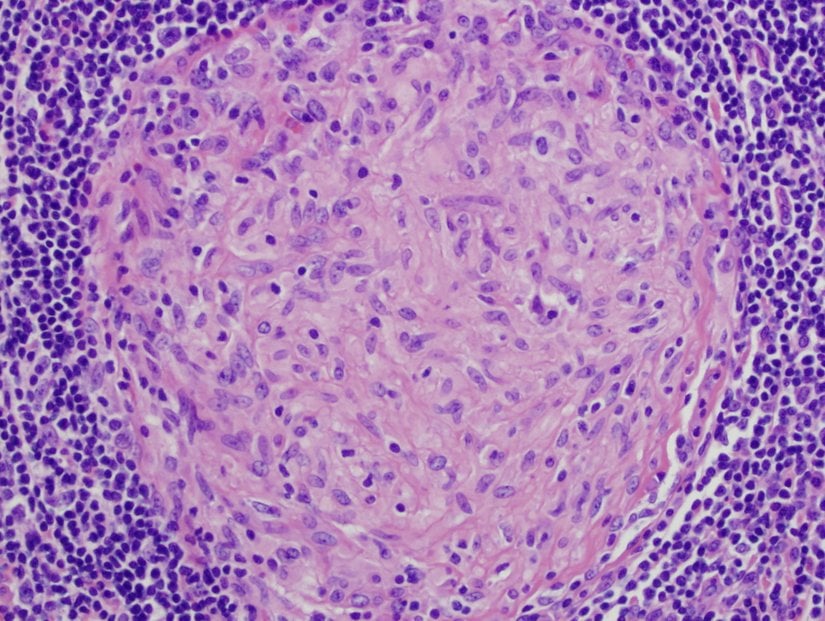

Kronik inflamasyon granülom oluşumuna yol açabilir. Granülomlar enfekte dokunun WBC'lerle çevrilmesinden oluşan keseciklerdir. Makrofajlar ve diğer fagositler granülom içindeki patojenleri ve ölü hücresel materyalleri ortadan kaldırmak için bir savaş verseler de başarılı olamazlar. Kronik inflamasyon üreten hastalıklara bir örnek, akciğer dokularında granülom oluşumuna neden olan tüberkülozdur. Tüberküloz granülomuna tüberkül denir.